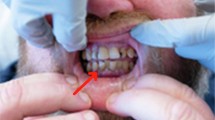

ALTHOUGH scurvy was probably the first clearly defined nutritional disease and active antiscorbutic material was the first of all the vitamins to be crystallized and synthesized, the biochemical function of ascorbic acid in synthesis of collagen has only recently been identified. Some of the proline residues of the collagenous poly-peptide are hydroxylated to form hydroxyproline, and ascorbic acid is a co-factor for the hydroxylating enzyme1. Most pathological findings in scurvy can be attributed to a restriction in ability to synthesize collagen of bone, teeth and other connective tissues. Some manifestations occasionally found in infantile scurvy are more prominent in adult scurvy and are difficult to explain by a restriction in ability to synthesize collagen of connective tissues. For example, the cutaneous haemorrhages or “scorbutic spots” appearing spontaneously about hair follicles are one of the cardinal signs of adult scurvy2.